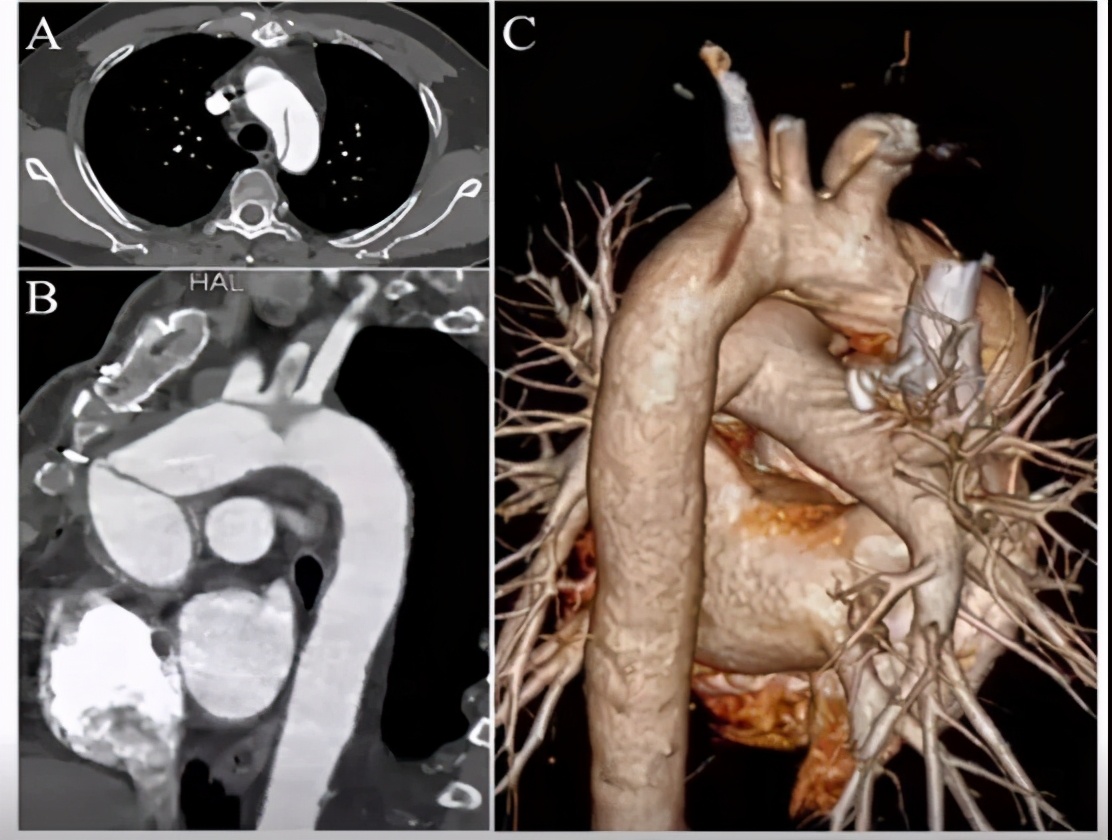

全主动脉cta三维重建影像提示:左锁骨下动脉起源于主动脉瘤体,左颈